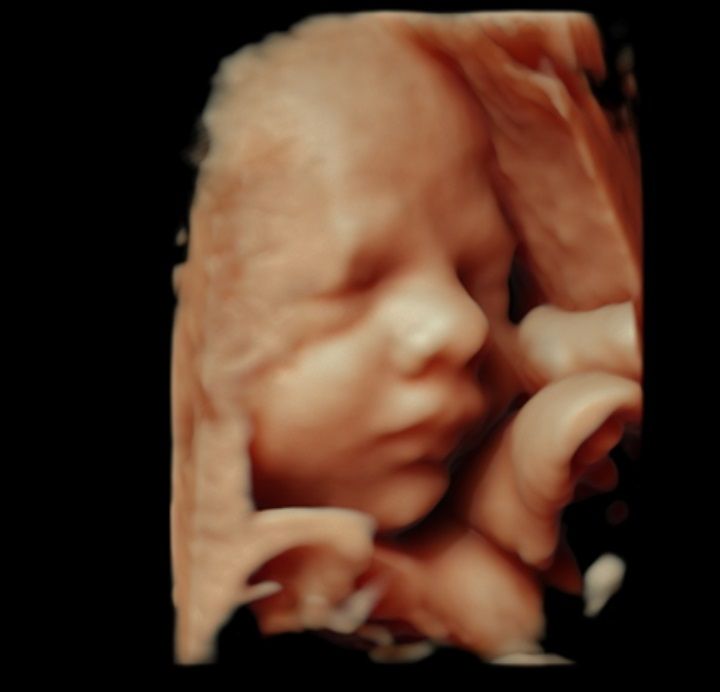

3D/4D HD live Standard - 2000kr

Kan göras mellan 26+0 till 34+0. De mest populära veckorna med bäst resultat är mellan 27+0 till 29+0.

- Minst 10 digitala 3D/4D bilder.

- 2 utskrivna Färgbilder i 3D.

Skillnad mellan 3D och 4D: Ett 4D ultraljud visar barnets rörelser, liknande en 3D-video. Ibland kan vi fånga när barnet leker eller gör ansiktsuttryck, men det är inte alltid möjligt.

Bildkvalitet: Kvaliteten påverkas av fostrets position, fostervattenmängd och mammans BMI; mer fostervatten och normal BMI ger oftast bättre bilder. Det finns dock inga garantier för bildens kvalitet.